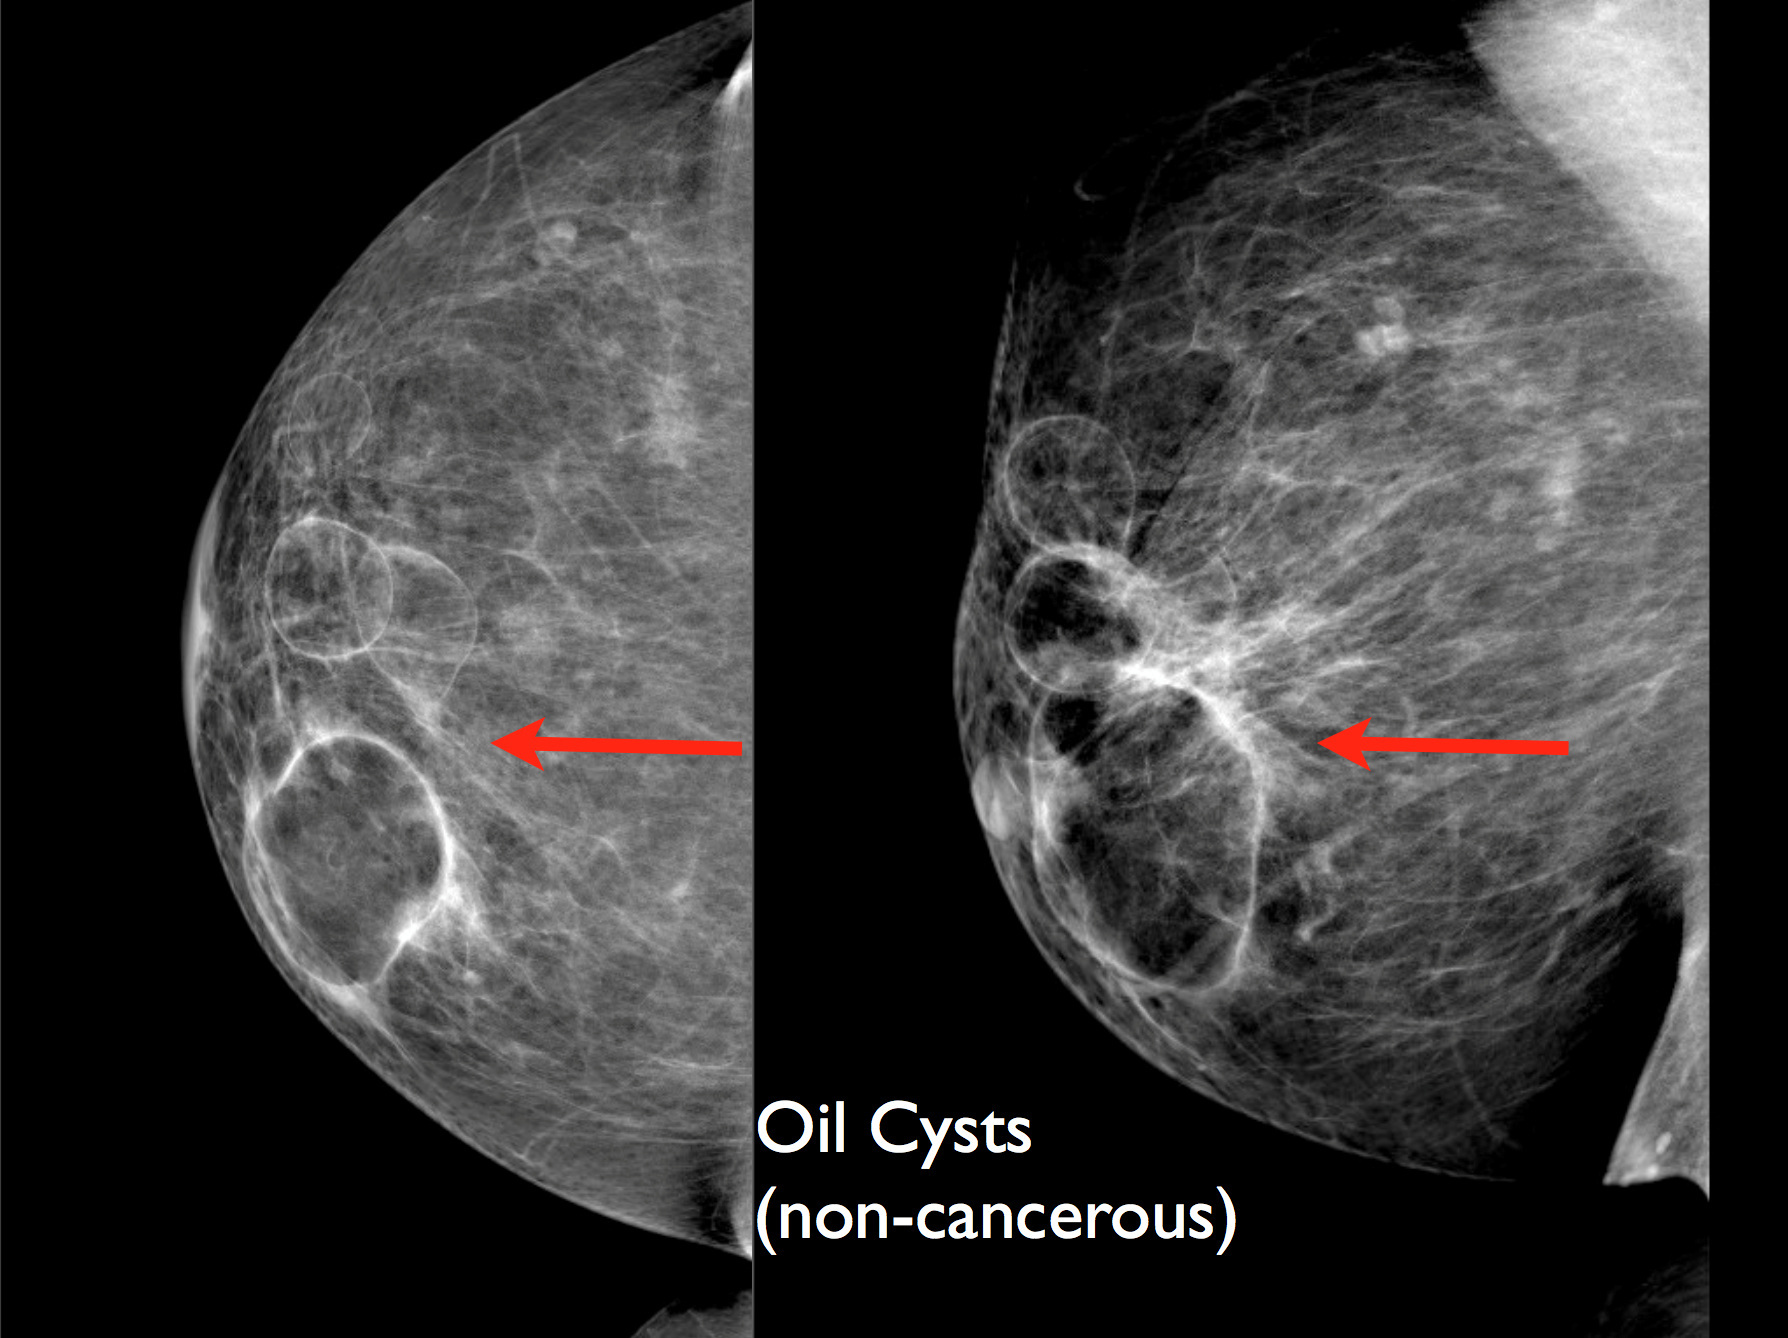

Киста на снимке маммографии